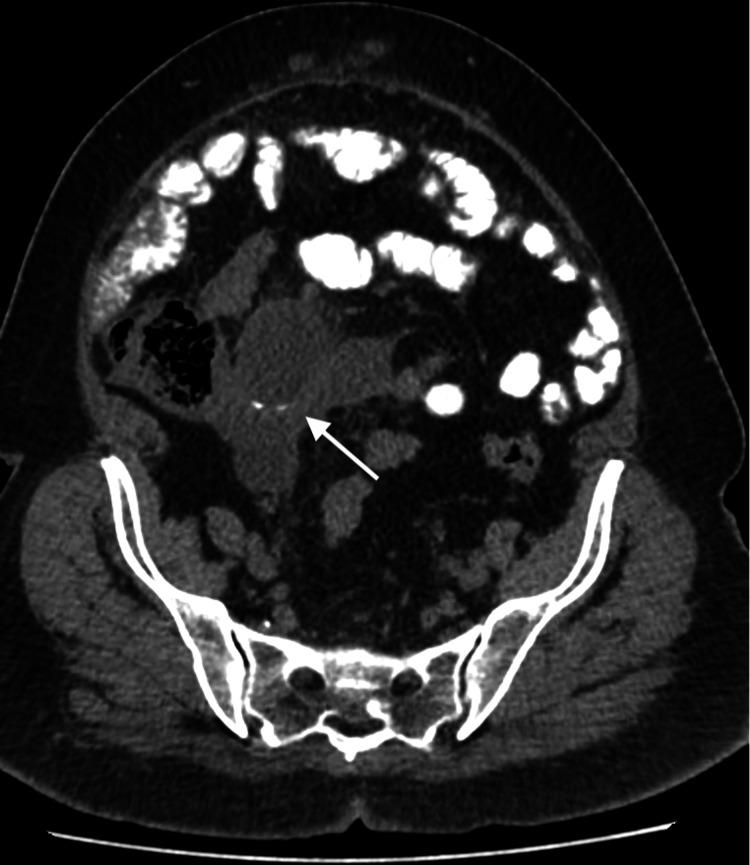

Mucocele of the appendix (MA) is a rare disease characterized by chronic accumulation of mucin within an appendix. Although MA can be an asymptomatic finding, some patients with MA may present with right lower quadrant (RLQ) pain, pelvic pain, or even hernias. The later presentation is usually related to rupture of the mucin-filled appendix, a condition referred to as pseudomyxoma peritonei (PMP). Herein, we present a case of ruptured MA presenting as an irreducible paraumbilical hernia, where the patient presented with a lump to the surgical clinic. computed tomography (CT) of the abdomen revealed an RLQ lesion extending through the hernial neck. Further characterization of the lesion was performed with magnetic resonance imaging (MRI), revealing an appendiceal origin of the lesion. The patient underwent an exploratory laparotomy during which an omental sample was taken. Histopathology confirmed the diagnosis of metastasizing low-grade appendiceal mucinous neoplasm. We believe that our case is unique due to the rarity of ruptured MA as well as the rarity of it presenting as a paraumbilical hernia.

阑尾黏液囊肿(MA)是一种罕见疾病,其特征为阑尾内黏液的慢性积聚。尽管MA可能是无症状表现,但一些MA患者可能出现右下腹(RLQ)疼痛、盆腔疼痛,甚至疝气。后期表现通常与充满黏液的阑尾破裂有关,这种情况称为腹膜假黏液瘤(PMP)。在此,我们报告一例破裂的MA表现为不可复性脐旁疝的病例,该患者因肿块到外科门诊就诊。腹部计算机断层扫描(CT)显示一个RLQ病变延伸至疝颈。通过磁共振成像(MRI)对病变进行进一步特征分析,显示病变起源于阑尾。患者接受了剖腹探查术,术中取了网膜样本。组织病理学证实为转移性低级别阑尾黏液性肿瘤。我们认为我们的病例很独特,因为破裂的MA罕见,且表现为脐旁疝也罕见。